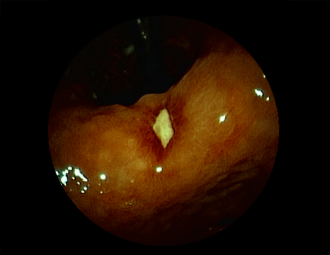

症例1:胃潰瘍(37才、男性)

①胃潰瘍(Stage A1)

健診:胃レントゲン検査で、胃角部ニッシェを指摘され当院受診。

胃角部小弯に、深くて大きな、大きさ約10mmの胃潰瘍(stage 1)

があり、潰瘍底は一部白苔はみ出しを認める。エソメプラゾールマグネシウム水和物投薬で治療開始しました。

(FICE画像)